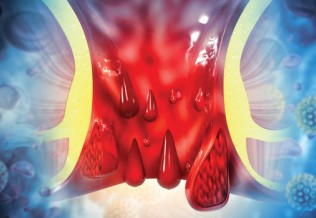

- la plus fréquente est l’hémorragie digestive, qui se présente sous forme d’hématémèse et/ou de méléna et/ou d’anémie plus ou moins aiguë ;